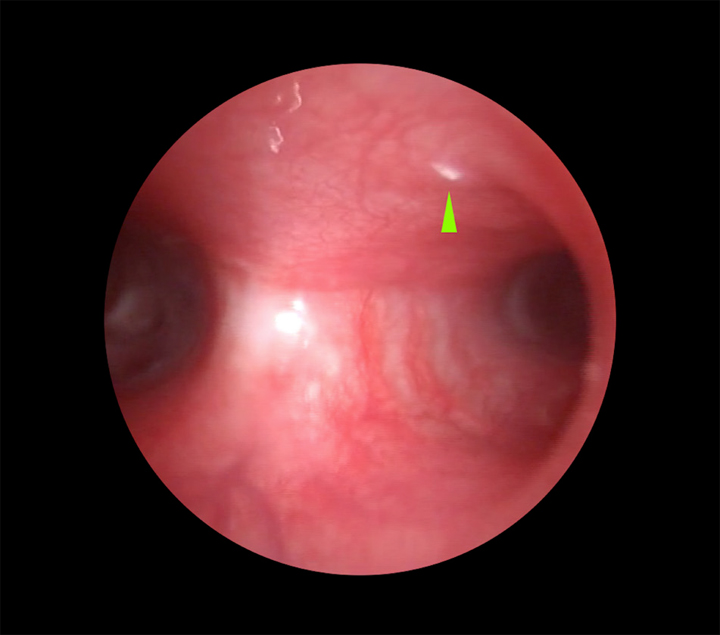

Tras la premedicación de la paciente mediante la combinación de clorhidrato de medetomidina (Domtor, Ecuphar Veterinaria, SLU, Barcelona), a 7 μg/kg por vía intramuscular y de tartrato de butorfanol (Torphasol, Ecuphar Veterinaria, SLU, Barcelona), a 0,4 mg/kg también vía intramuscular, y previamente a su inducción con propofol (Propofol Lipuro 1% , B. Braun Vetcare, SA, Barcelona) a 2,5 mg/kg vía intravenosa, se procedió a la exploración endoscópica de la laringe y primer tercio de la tráquea mediante el empleo de una óptica rígida de 0º, 5 mm de diámetro y 8,5 cm de longitud, con el fin de valorar su estructura y función dinámica. Se descartó tanto la existencia de alteraciones en la dinámica laríngea (parálisis o paresia laríngea), así como en su estructura (colapso laríngeo), pero se demostró la presencia de moderado eritema de la mucosa laríngea asociado a la existencia de una forma larvaria compatible con L1 de Oestrus sp. a nivel del vestíbulo laríngeo (Fig. 1).

<p>Imágenes endoscópicas de la laringe. (<strong>A</strong>) Presencia de congestión focal laringitis. (<strong>B</strong>) Presencia de L1 de <em>Oestrus</em> sp. en vestíbulo laríngeo (punta de flecha verde).</p>

Imágenes endoscópicas de la laringe. (A) Presencia de congestión focal laringitis. (B) Presencia de L1 de Oestrus sp. en vestíbulo laríngeo (punta de flecha verde).